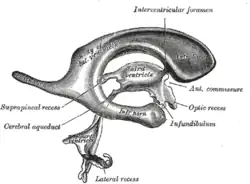

Fallbeispiel I: Normaldruckhydrozephalus

Ein 71 Jahre alter männlicher Patient wird von den Angehörigen in die neurologische Sprechstunde gebracht. Man berichtet, der Großvater sei in letzter Zeit wiederholt gestürzt, habe sich aber nicht verletzt, außerdem sei er vergesslich geworden und man habe festgestellt, dass er Probleme beim Wasserlassen habe. Auf gezieltes Nachfragen berichten die Angehörigen, dass die Beschwerden mit der Zeit kamen und das Ganze sich schon mindestens zwei Jahre hinzieht. Dann wird der Patient körperlich untersucht. Der Neurologe fordert den Patienten auf, durch das Zimmer zu gehen: Er zeigt ein schwerfälliges Gangbild und hebt beim Laufen die Füße nur wenig an. Die Arbeitshypothese lautet nun: eine Demenz mit Blasenentleerungsstörung und sogenanntem „magnetischem“ Gang, die seit etwa zwei Jahren besteht und mit Zunahme der Beschwerden einherging, könnte ihre Ursache in einem sich langsam entwickelten Hydrozephalus haben. Zunächst wird eine CCT des Schädels durchgeführt. Man erwartet aufgrund des vermuteten Hydrozephalus sogenannte ballonierte Seitenventrikel mit einer randständigen und bevorzugt frontalen Hypodensität. Da das CCT diesen Befund zeigt, wird eine therapeutisch-diagnostische Maßnahme durchgeführt: beim sog. Fisher-Test wird mittels einer Lumbalpunktion probeweise ca. 30 bis 40 ml Nervenwasser entnommen. Diese Maßnahme sollte die Beschwerden bessern. Beim Test zeigt sich kein erhöhter Liquordruck. Etwa 10 Minuten nach der Lumbalpunktion zeigt der Patient ein gebessertes Gangbild. Seine Gedächtnisstörung wird unbeeinflusst bleiben und die Harninkontinenz wird sich später am ehesten verbessern. Der Patient wird mit der Diagnose eines Normaldruckhydrozephalus zum Neurochirurgen überwiesen zur Implantation eines ventrikulo-peritonealen Shuntsystems zum Zweck der dauerhaften Ableitung überschüssigen Nervenwassers.